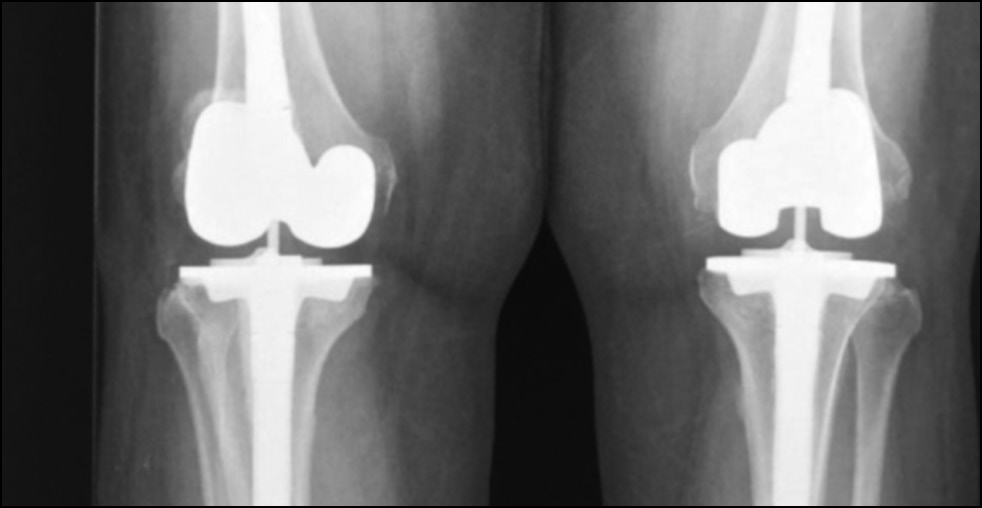

CASE 2. PATIENT 3

Age: 67 years.

Sex: Female.

Diagnosis: Bilateral advanced knee osteoarthritis.

Procedure: Bilateral simultaneous knee arthroplasty.

Associated illnesses: DM and hypertension.

Postoperative follow-up: No postoperative complications were encountered.

Length of hospital stay: 6 days.

Radiological assessment (Fig. 15–18)

Fig. 15. Ap preoperative x-ray showing bilateral knee osteoarthritis.

Рис. 15. Предоперационная рентгенограмма с двусторонним остеоартритом коленного сустава.

Fig. 16. Lateral preoperative x-ray right and left knees showing osteoarthritis.

Рис. 16. Предоперационная боковая рентгенограмма правого и левого колена с признаками остеоартрита.